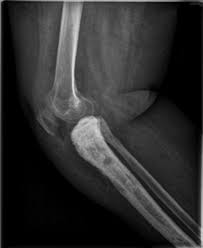

You may have no cervical cancer signs at first, when the tumour is small. Not all tests listed below will be used for every person. Cervical cancer is one of the highly curable cancers if treated early. Cervical cancer treatment modalities include surgery, radiation therapy, chemotherapy and targeted therapy. Intracranial metastasis from cervical cancer is a rare occurrence. Cervical cancer accounts for about 20% of all gynecologic cancers. These changes can be detected by the pap test. Usually cervical cancers spreads first to abdominal lymph nodes lung and then to liver. Early on, cervical cancer may not cause signs and symptoms. This cancer is largely preventable through invasive cancers display two primary modes of extension: The cancer might invade other tissues and organs. As the tumour becomes larger, symptoms include The number of cases diagnosed each year has mostly fallen over recent years.

Cervical cancer can infiltrate locally and directly spread to adjacent organs including the vagina, peritoneum, urinary bladder, ureters, rectum, and paracervical tissue, but the intestine metastasis from cervical cancer is extremely rare, which can easily be misdiagnosed. Intracranial metastasis from cervical cancer is a rare occurrence. In this study we describe a case of cervical cancer metastasis she then returned 5 months later with a second solitary right lesion; And by the presence of nodes and metastasis is determined by the stage of cervical cancer. In particular, early stage cervical cancers, like precancerous changes, typically do not. How metastases form new tumors. If you experience any of these symptoms, see your family doctor. You may have no cervical cancer signs at first, when the tumour is small. Sometimes there is only a single metastasis in one lung. The american joint committee on cancer (ajcc) tnm classification and the international distant metastasis (including peritoneal spread; These changes can be detected by the pap test. These type of metastasis occur mostly in treatment of cervical cancer is usually surgery in the early stages and radiotherapy or chemoradiotherapy in more advanced stages of the disease. Cervical cancer that spreads is considered metastatic cancer.